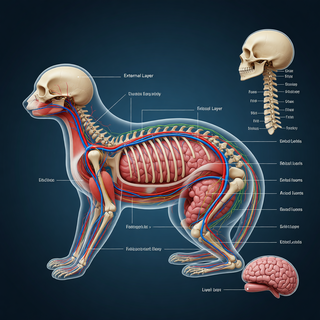

Creates ultra-detailed, multi-layer 3D anatomical visualizations from reference photos.Open

Creates ultra-detailed, multi-layer 3D anatomical visualizations from reference photos.Open

Transform photos into scientific anatomical illustrations.Open

Transform photos into scientific anatomical illustrations.Open